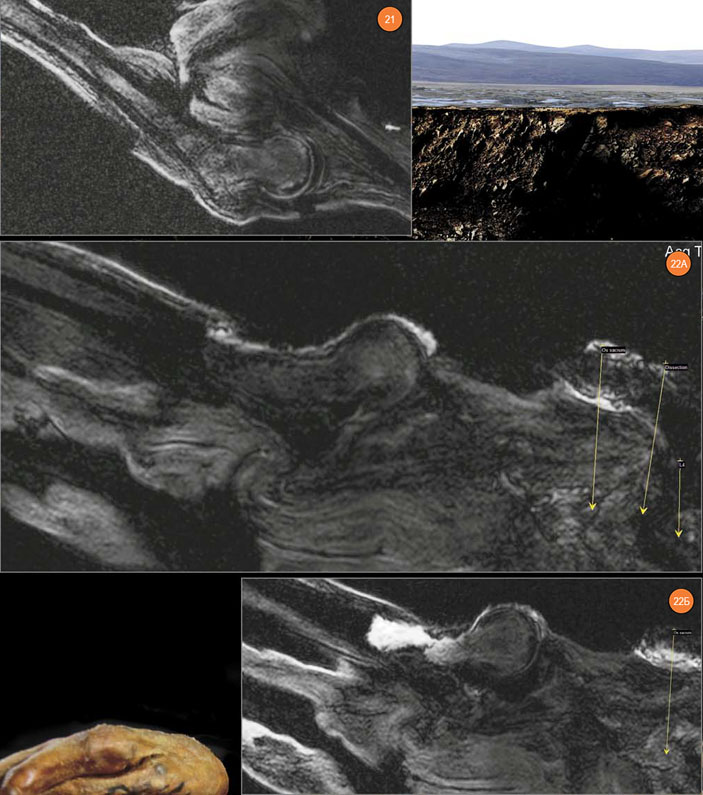

Рис. 21. Левый тазобедренный сустав. Рис. 22. Правый тазобедренный сустав. А — имеется резкая отечность в области шейки и в межтрохантерной зоне (внутри сустава, видна «пустая» гленоидальная полость), Б — головка бедренной кости вывихнута за пределы края гленоидальной полости

Капсула этого сустава имеет явную отечность со скоплениями жидкости внутри суставной капсулы, с выраженной отечностью в прилежащей клетчатке правой паховой области. Именно эти данные позволяют утверждать, что изменения правого тазобедренного сустава носят прижизненный характер. В сочетании с травматической деформацией головки правой плечевой кости, деформацией передней крестообразной связки правого коленного сустава (о которой речь пойдет ниже) и деформации поясничного отдела позвоночника по типу сублистеза они дают основания предположить значительную прижизненную травму. Это могло произойти при падении с лошади.